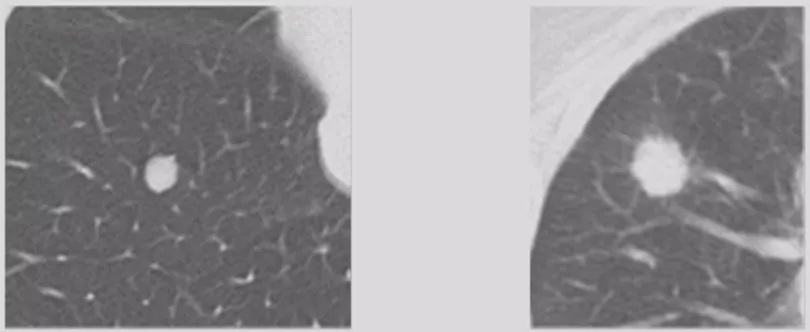

内部特征——钙化

30年前的影像学理论曾提到,结节里如果有钙化就强烈提示为良性病变。但是现在的研究结论则表明,良性病变钙化多为弥漫实性、中央型、边缘型、爆米花型、板层状钙化;恶性病变主要为散在、偏心点状钙化(数量少);位于尖段新发的、缓慢生长的钙化结节须随访。现在出现钙化不足以为一个独立的证据,所以要谨慎对待钙化。

「爆米花样」钙化

这两种爆米花样的钙化和层状的钙化,是错构瘤。

层状钙化

一层一层的钙化多见于良性病变。